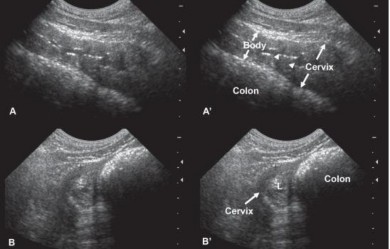

Hình 2.5. Hình ảnh giai đoạn nghỉ ngơi bình thường của giống chó Scottish Terier 6 tuổi

Nguồn: Rachel Pollard & Silke Hecht (2015)

Hình 2.6. Hình ảnh giai đoạn trước động dục ở giống Labrador Retriever 6 tuổi